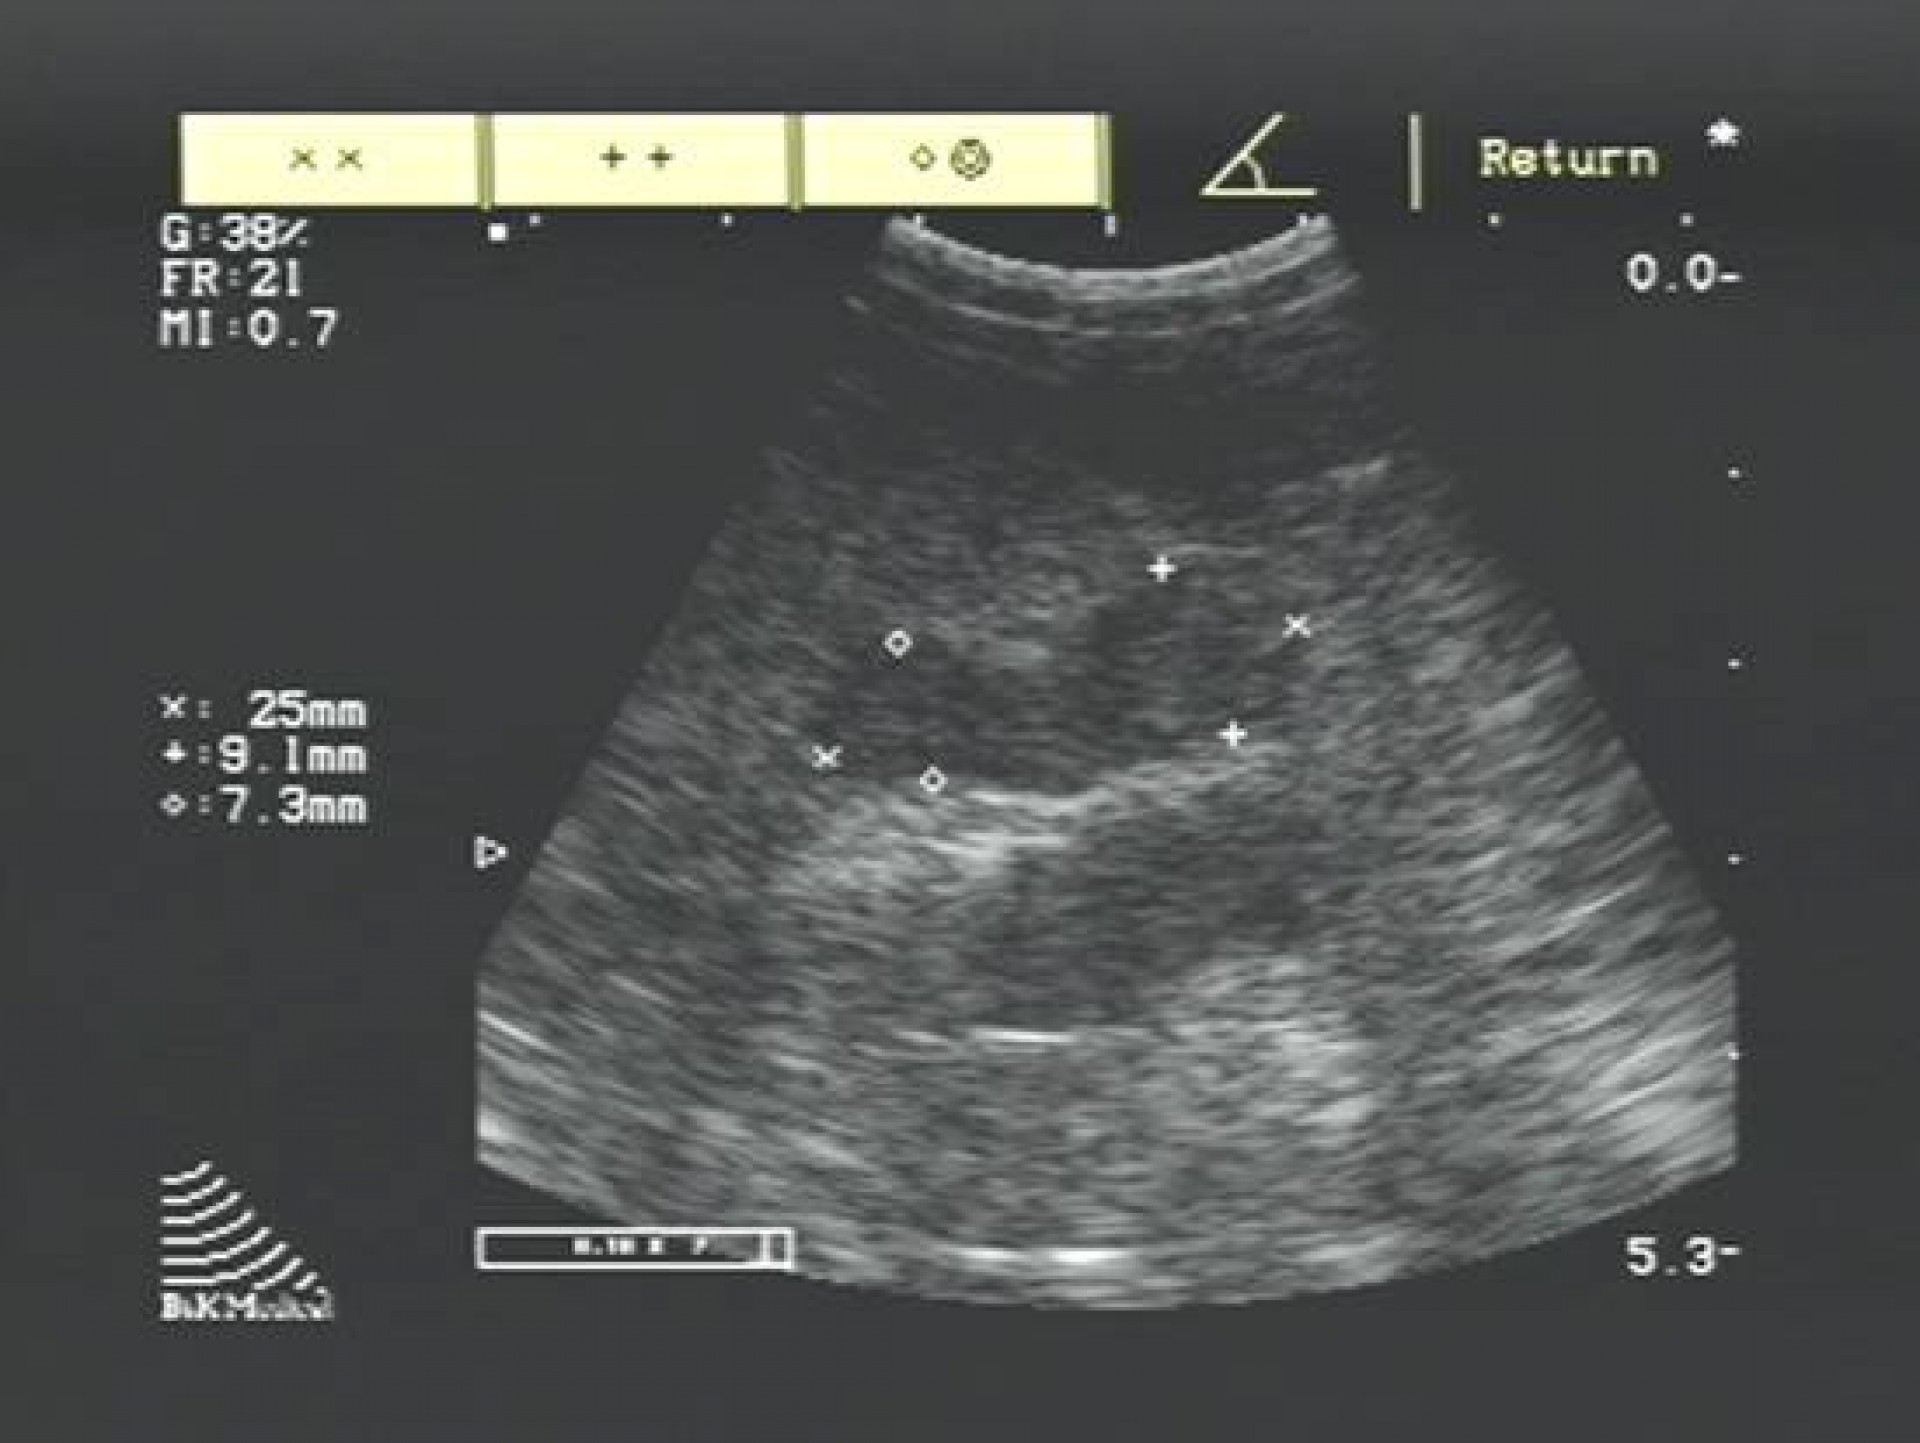

A betegség diagnosztizálása hasüregi ultrahangos vizsgálattal és vérvizsgálattal történik, mely során különös figyelmet kell fordítani a perifériás és centralis forma elkülönítésére.

A daganatos mellékvesét az azonos oldali vese előtti területen a bordaív alatt találjuk meg.